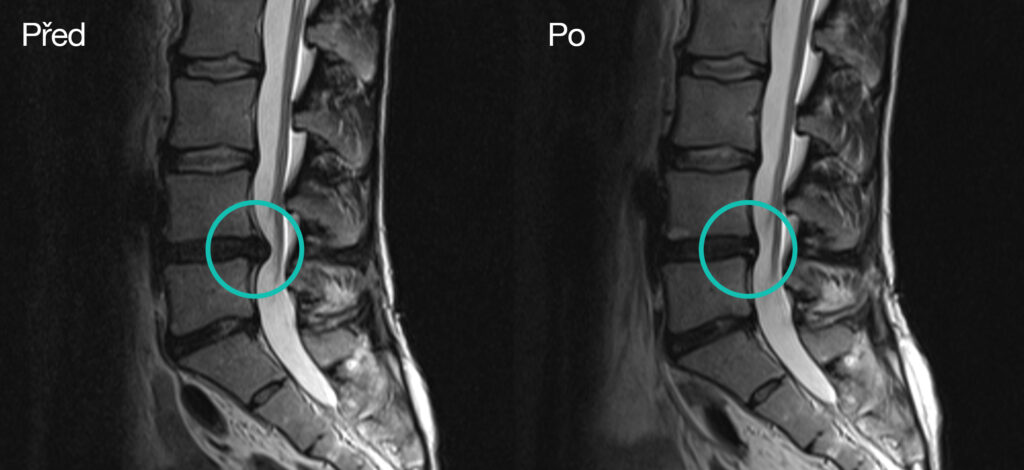

Bild links: Vor der Behandlung, 34-jährige Frau

Bild rechts: nach 1-jährigem täglichem trainieren und manueller Therapie, schmerzfrei